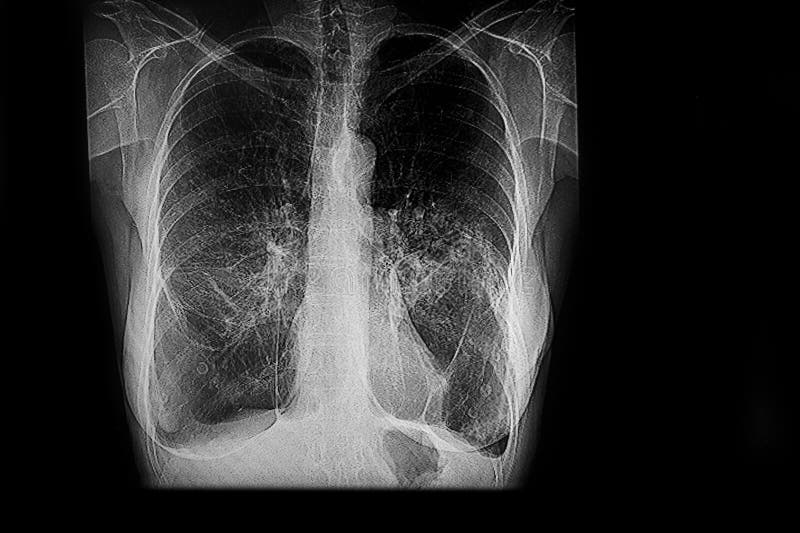

When people hear the term lower respiratory tract disease, they often think only of pneumonia or severe infections. In reality, this category covers a broad range of conditions that affect the deepest and most vital parts of the breathing system – the bronchi, bronchioles, and lungs themselves. These structures are responsible for oxygen exchange, making their health essential to every cell in the body.

The lower respiratory tract begins at the trachea and branches downward into the bronchi and bronchioles, ending in the alveoli – tiny air sacs where oxygen enters the bloodstream and carbon dioxide is removed.

Each condition differs, but they share a common theme: restricted airflow and compromised oxygen exchange.